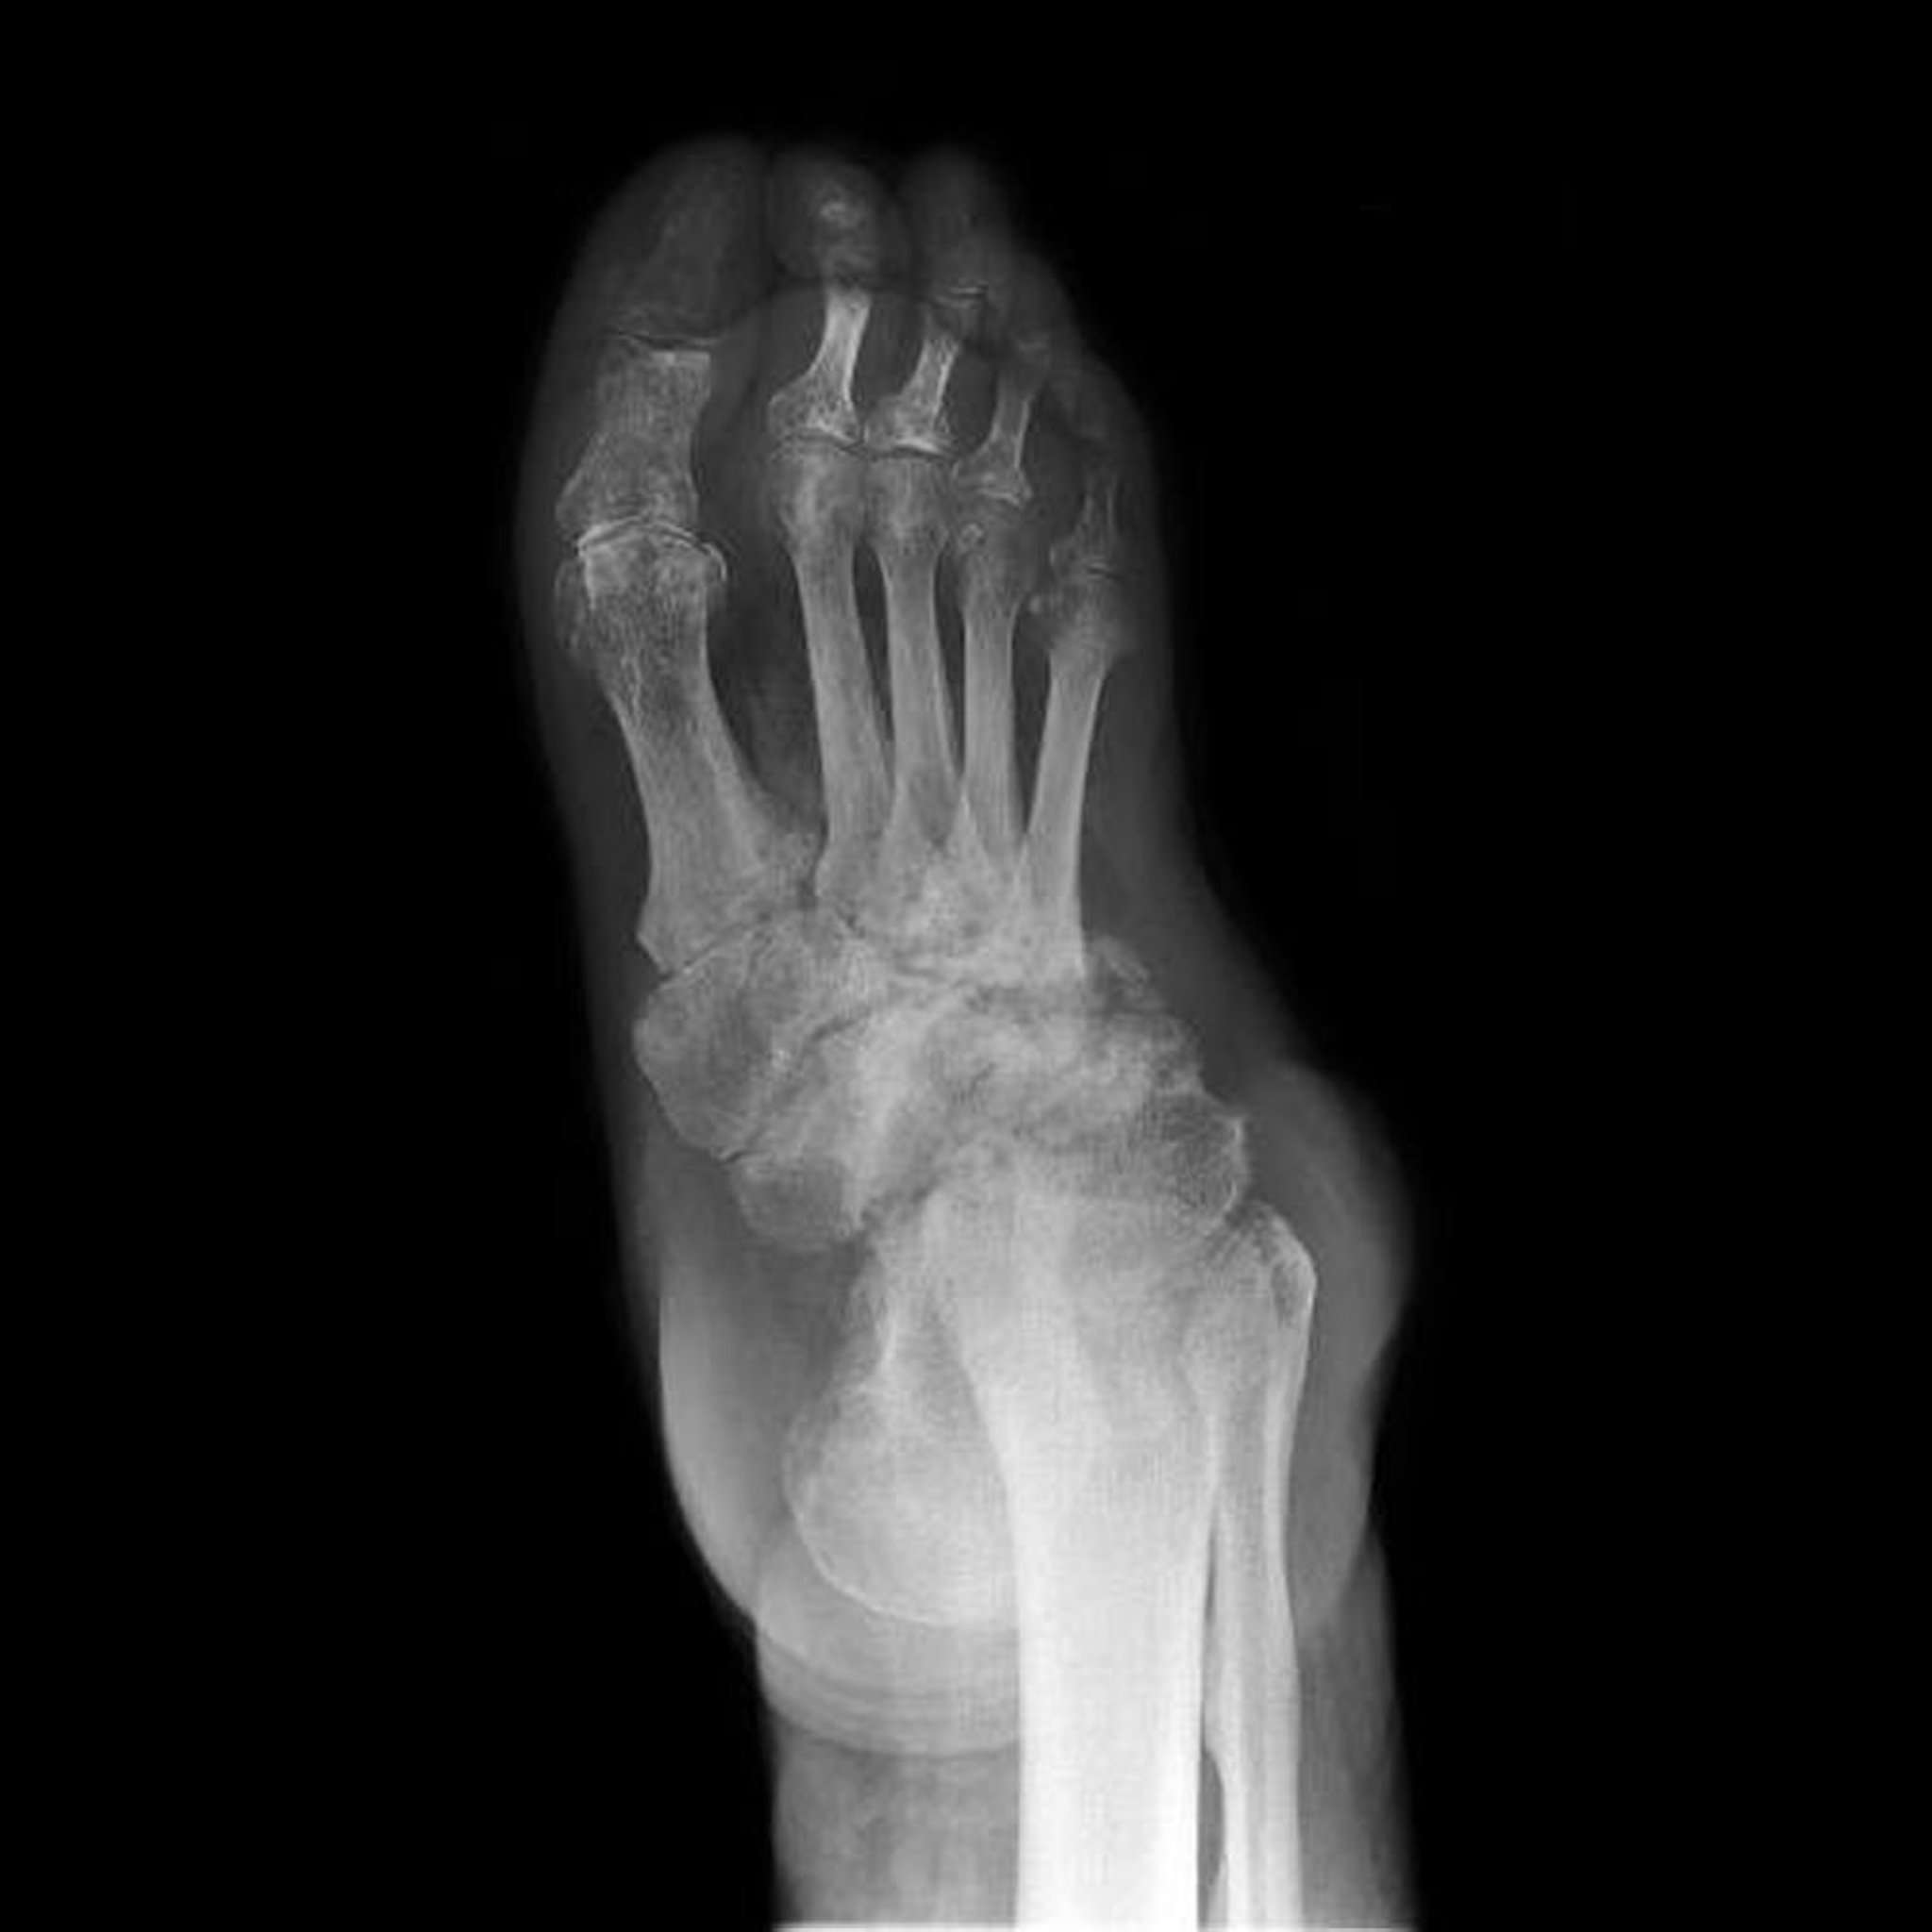

This radiograph shows neuropathic arthropathy of the foot (also known as Charcot foot). Destruction, deformities, and loss of joint spaces of the tarsal bones is extensive.

Невропатична артропатія стопи